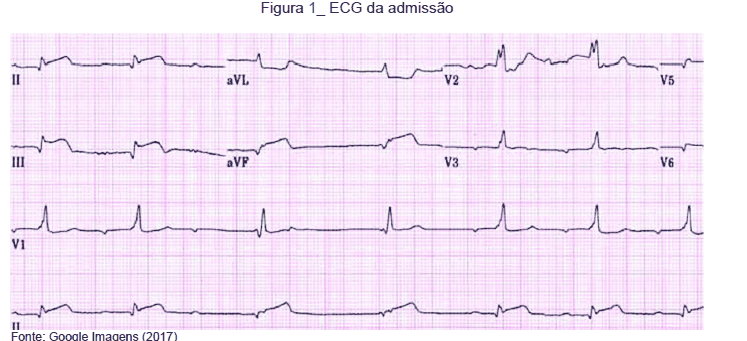

Paciente de 34 anos realizou ecocardiograma transesofágico no intraoperatório.

De acordo com as imagens apresentadas nas figuras A e B, ambas em sístole ventricular, é correto afirmar que a figura